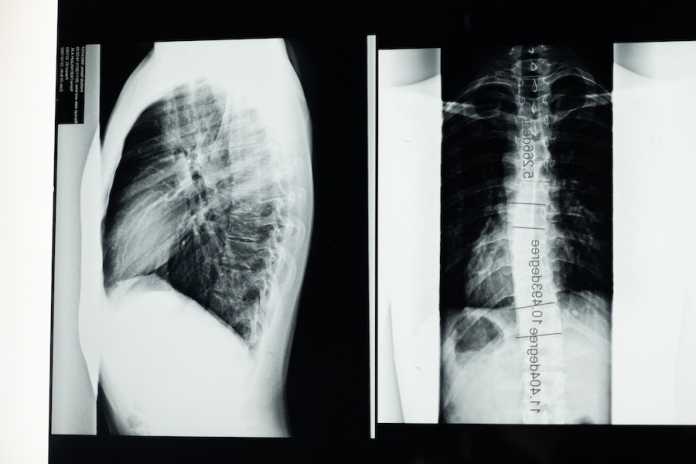

Πρόκειται για την Χρόνια Αποφρακτική Πνευμονοπάθεια (ΧΑΠ), η οποία αποτελεί χρόνιο αναπνευστικό νόσημα με περιορισμό στην εκπνοή λόγω απόφραξης ή καταστροφής τμημάτων του πνεύμονα.

Με 3,23 εκατομμύρια θανάτους από ΧΑΠ να έχουν καταγραφεί το 2019, αποτελεί την 3η αιτία θανάτου παγκοσμίως. Για τον λόγο αυτό έχει καθιερωθεί και η Παγκόσμια Ημέρα Χρόνιας Αποφρακτικής Πνευμονοπάθειας, που φέτος είναι η 17η Νοεμβρίου, με στόχο την ευαισθητοποίηση του ευρέως κοινού, αλλά και την ενημέρωση των πασχόντων ή των δυνητικά πασχόντων, έτσι ώστε να είναι σε θέση να αντιμετωπίσουν σωστά την κατάστασή τους.